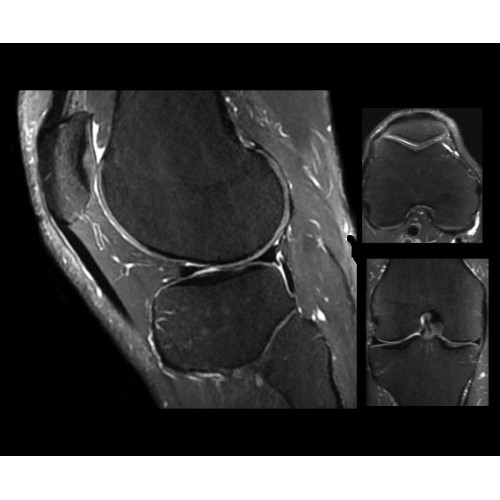

• OrthoWorks — программное решение для визуализации структур опорно-двигательного аппарата с прекрасным контрастированием тканей.